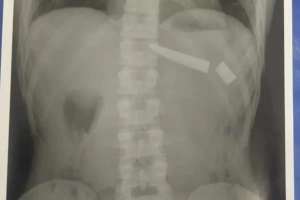

Segundo a PM, os dois homens começaram a brigar e o suspeito, que também tem 25 anos, esfaqueou a vítima nas costas e na região dos rins. Segundo a polícia, a faca quebrou em dois lugares do tórax.

Ele foi socorrido pelo Serviço de Atendimento Móvel de Urgência (Samu) e encaminhado para o Hospital de Urgências de Goiás (Hugo). Segundo o hospital, o paciente já passou por cirurgia e está se recuperando.